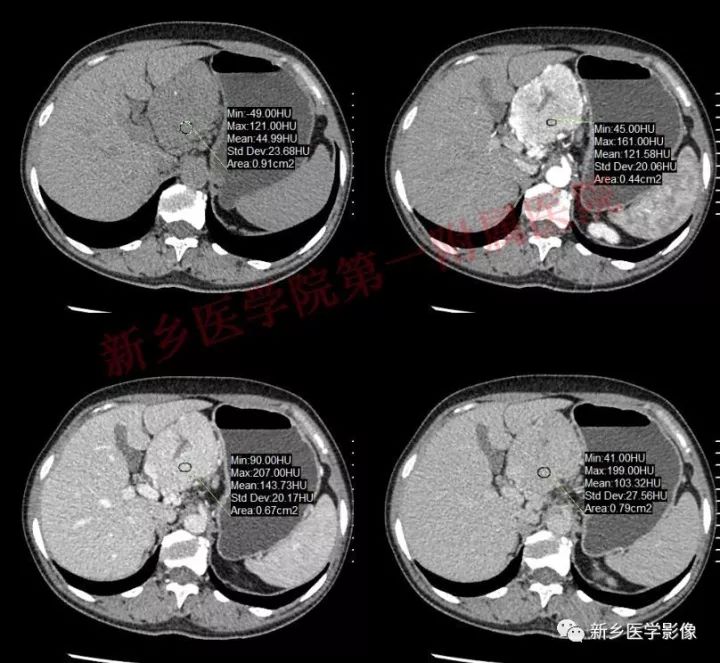

肝胃间胰腺前上方见类圆形肿块,边界较清,大小约8.2cm×4.6cm×5.9cm,密度欠均匀,内见点状钙化,增强呈不均匀明显强化,内见片状低密度灶无强化区,其下部与相邻胰腺分界不清,周围见粗大回流血管影回流至门静脉,病变左侧及腹膜后、胃壁小弯侧见数个卵圆形稍大淋巴结及结节影,部分呈环形强化。

GLNH高强化机制为透明血管型病灶内丰富的毛细血管增生和周边较多粗大的滋养动脉所致。

GLNH钙化较少,可见于5%~10%的病例,且仅见于局限型透明血管型。

GLNH另一个特征是瘤灶内极少伴有出血和坏死灶,尽管部分病例呈不均匀性强化,但瘤灶内的低密度影并非坏死灶。